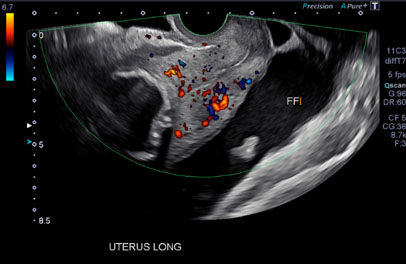

A subsequent transvaginal ultrasound showed a large volume of free fluid within the pelvis, a soft tissue nodule separated but superior to the left ovary with Doppler flow, and an enlarged uterus with a calcified fibroid (Figure 2).

Figure 2: Transvaginal ultrasound revealing large amount of free fluid in pelvis.